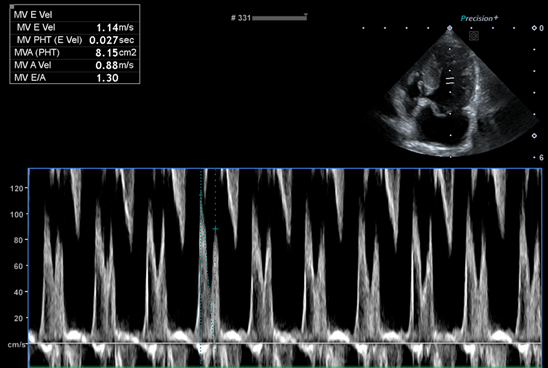

심장 초음파 보겠습니다

좌심방의 압력을 간접적으로 나타내는 E vel은 많이 낮아졌습니다.

(보통 1.5m/s가 넘으면 폐부종이 터진 상황이거나 터지기 직전 상황입니다)